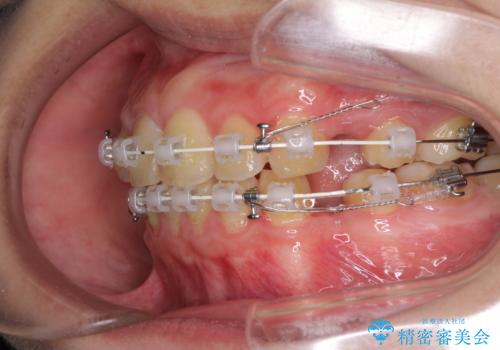

- 審美装置

- 2年3ヶ月

- 口元が出てるのが気になるとのことで来院されました。

歯のがたつきはあまりなかったのですが、口唇が閉じずらく、口元の突出感が確認できました。

上下左右の歯を1本ずつ抜歯して、そのスペースを利用して口元を引っ込める計画としました。